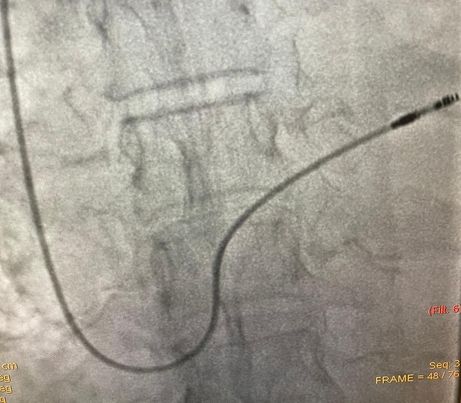

قام الدكتور محمد ذردق استشاري كهربية القلب، ومدرب زمالة كهروفسيولوجية القلب، وبمساعدة الدكتور محمد هاني بحيري أخصائي القلب بمستشفي الزقازيق العام، بتركيب منظم دائم للقلب، لمريض متواجد بوحدة العناية المركزة للقلب بمستشفي الزقازيق العام، وذلك بعد إجراء كافة الفحوصات الطبية اللازمة، والحالة الآن مستقرة وتحت الملاحظة الطبية، بإشراف أطباء القلب والقسطرة ورئيس القسم ومدير المستشفي.